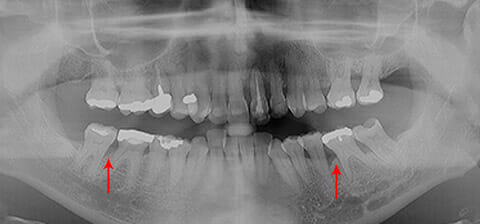

Panoramica prima della della terapia parodontale